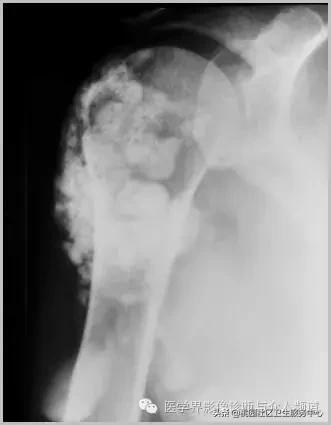

五、滑膜软骨瘤病

1°少见,病灶数量多,大小均匀,相邻关节正常。

2°多见,病灶数量少,大小不一,多伴有退行性骨关节病。

滑膜骨软骨瘤病 1°

滑膜骨软骨瘤病 2°

滑膜骨软骨瘤病